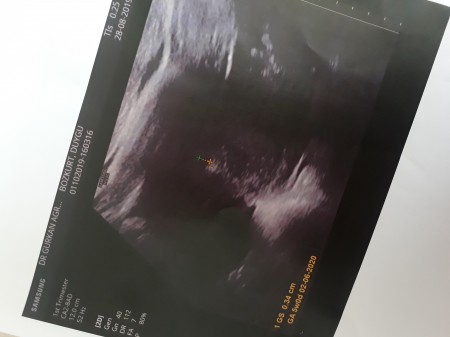

Önceden de sormustum hamile miyim siz  diye sonradan cikmisdi cizgim :) . Dun muayne  icin gittim ve 5 haftalik  hamileymisim . Goruntude keseye cok benzetemedim ama :)) haftaya tekrar gel.embriyoyu gormem lazim dedi cok heyecanliyim. Hamileliğim sanirim kesjnlesti ama insallah sorun cikmaz.  Haftaya acaba gorebielcek miyiz bebegi cok heyecanliyim. Rabbim herkesin yavrusunu kucağına  almayi nasip etsin

Gebelik haftası 5.hafta